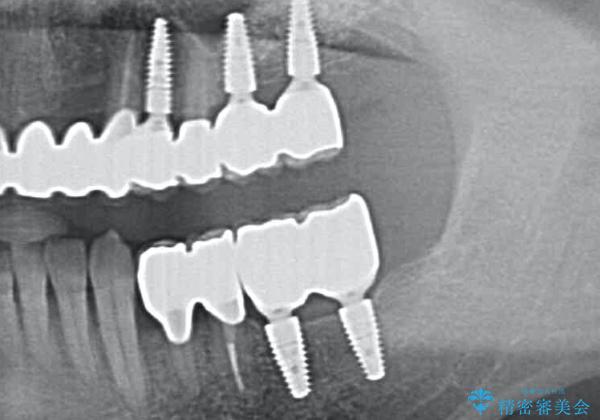

[ 重度歯周病 ] 骨造成・インプラント治療による咬合機能の回復

歯周病治療を徹底的に行ったことで、残った歯の歯周ポケットはなくなり、奥歯のインプラントがあることでしっかりとかめるような咬合関係が確立されました。